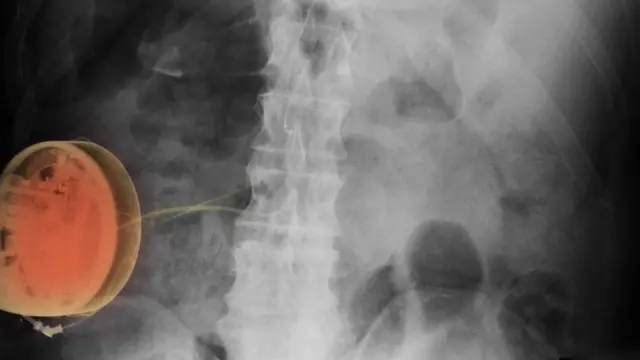

Причиной боли оказался панкреатит.

Ей назначили курс антибиотиков и месяц спустя сделали операцию по удалению желчного пузыря.